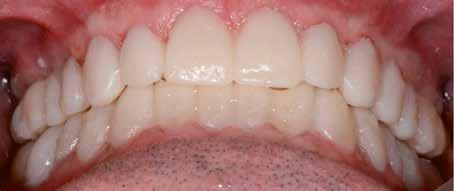

Hölgy páciensem az első konzultáció során tipikus kórtörténetet vázolt fel: Gyermekkora óta szeretett volna fogszabályozó készüléket, hiszen mindig is zavarta a class 2-es eltérésnél tipikusan jellemző nagy overjet (1-3. képek), és természetesen az ezáltal kifelé álló felső metszőfogai, részben a felső metszők protrúziója, részben pedig a disztálisan elhelyezkedő mandibula miatt. Annak ellenére, hogy több fogszabályozó szakorvosnál is járt az évek során, de mivel saggitális eltérése és az alsó metszőfogak torlódása miatt négy kisőrlőfog extrakcióját, illetve emellett sokszor állcsont műtétet is javasoltak neki, nem vágott bele a kezelésbe (4-5. képek).

A fogorvosa – nagyon helyesen – felhívta a figyelmét, hogy parodontális státusza is valószínűsíthetően romlani fog az eltérése miatt, újabb kört futott, immár 39 évesen, de még mindig premoláris fogak húzása és állcsontműtét nélkül szerette volna a fogszabályozást.

A konzultáció során arról is beszéltünk – ahogy az ilyenkor lenni szokott –, sohasem szeretett igazán mosolyogni, de a Pitts Protokolloknak köszönhetően az arc- és mosolyesztétikai céloknak megfelelően kerül megvalósításra az okklúziós korrekció. Az okklúziós kezelési célok az alábbiak voltak: a felső és alsó fogív nivellálása és tágítása, az alsó fogsor/ mandibula mezializálása, valamint a harapás megemelése által a mélyharapás rendezése.

A fogkontúrálás és az interproximális redukció alkalmazásával a mikroesztétikai részletek tökéletesítése is megtörtént (11. kép) A kezelés mindössze 16 hónapig tartott, megtörtént a rágófunkció helyreállítása, és az esztétikai végeredmény sokéves várakozás után valóban fordulópontot jelentett páciensünk életében (12-14. képek).